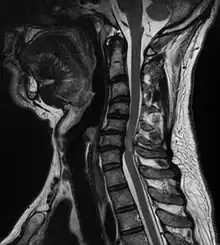

Compression médullaire

Une compression médullaire peut être décrite comme une déformation de la moelle spinale due à un hématome, une tumeur ou une simple hernie discale.

- Myélopathie cervicoarthrosique

- Hernie discale

- Syringomyélie